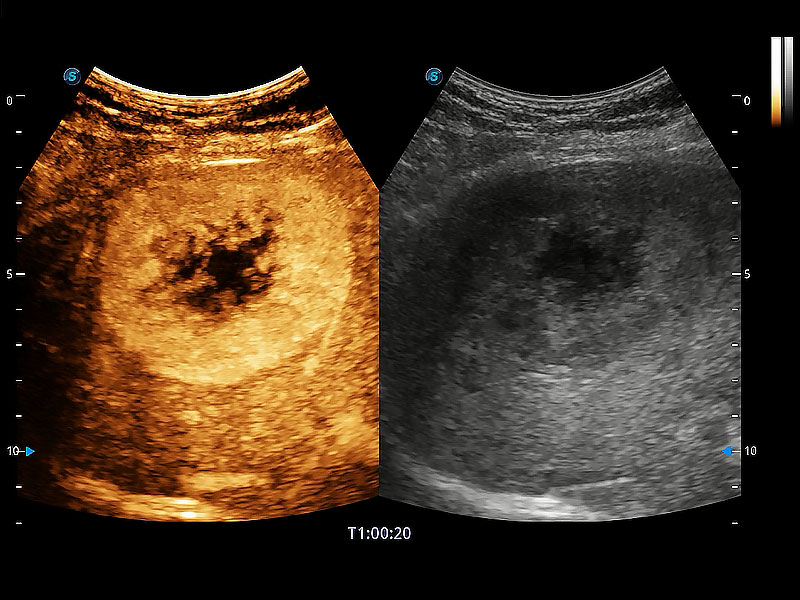

非線性融合造影成像充分利用諧波和基波信號,為難以觀察的血流進(jìn)行增強(qiáng)顯像??捎糜诰€陣、凸陣、微凸陣、相控陣探頭。

能夠增加心肌組織與血流之間的區(qū)別。對于心臟掃查困難的動物,可提供更好的心內(nèi)膜邊界的顯示。